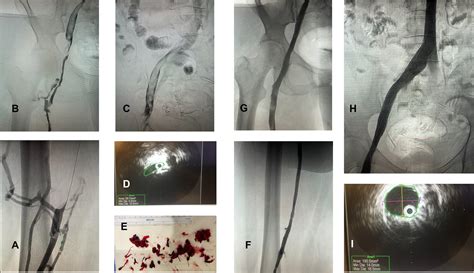

• Catheter-Directed Venography: Considered the gold standard. A contrast dye is injected, and live X-rays allow the doctor to see the exact site and severity of the venous obstruction.

Modern medicine favors endovascular techniques, which are less invasive than traditional open surgery. These procedures are usually performed by an interventional radiologist or vascular surgeon:

• Angioplasty: A small balloon is inserted into the vein and inflated to stretch the narrowed area, clearing the obstruction.

• Stenting: After angioplasty, a tiny metal mesh tube (stent) is permanently placed in the vein to keep it open and prevent the artery from compressing it again.

• Catheter-Directed Thrombolysis: If a DVT is present, medication is delivered directly into the clot to dissolve it safely.